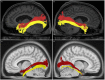

The human inferior longitudinal fasciculus (ILF) is a ventral, temporo-occipital association tract. Though described in early neuroanatomical works, its existence was later questioned. Application of in vivo tractography to the neuroanatomical study of the ILF has generally confirmed its existence, however, consensus is lacking regarding its subdivision, laterality and connectivity. Further, there is a paucity of detailed neuroanatomic data pertaining to the exact anatomy of the ILF. Generalized Q-Sampling imaging (GQI) is a non-tensor tractographic modality permitting high resolution imaging of white-matter structures. As it is a non-tensor modality, it permits visualization of crossing fibers and accurate delineation of close-proximity fiber-systems. We applied deterministic GQI tractography to data from 30 healthy subjects and a large-volume, averaged diffusion atlas, to delineate ILF anatomy. Post-mortem white matter dissection was also carried out in three cadaveric specimens for further validation. The ILF was found in all 60 hemispheres. At its occipital extremity, ILF fascicles demonstrated a bifurcated, ventral-dorsal morphological termination pattern, which we used to further subdivide the bundle for detailed analysis. These divisions were consistent across the subject set and within the atlas. We applied quantitative techniques to study connectivity strength of the ILF at its anterior and posterior extremities. Overall, both morphological divisions, and the un-separated ILF, demonstrated strong leftward-lateralized connectivity patterns. Leftward-lateralization was also found for ILF volumes across the subject set. Due to connective and volumetric leftward-dominance and ventral location, we postulate the ILFs role in the semantic system. Further, our results are in agreement with functional and lesion-based postulations pertaining to the ILFs role in facial recognition.